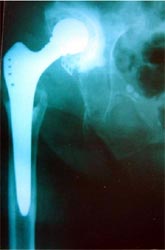

全髋置换术                                单纯股骨头置换术

如果股骨头和髋臼都已经破坏或者预期人工关节要使用很多年,需要进行全髋关节置换术。如果患者为高龄,可以进行单纯股骨头置换术。